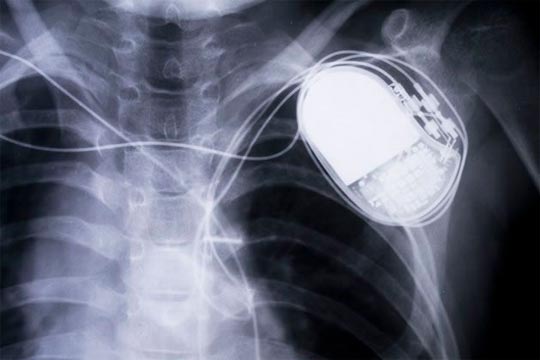

Com a capacidade de controlar marca-passos, bombas de insulina e até implantes de monitoração no cérebro, o número de cirurgias adicionais para manutenção dos equipamentos irá cair vertiginosamente, segundo os pesquisadores.